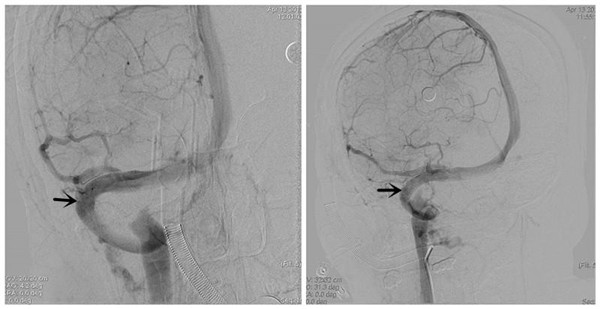

经过充分的术前准备,脑脊液鼻漏停止、颅内感染完全控制后。于4月13日在全麻下为患者行右侧横窦、乙状窦狭窄支架成形术。手术由牛晓丽主治医师麻醉,崔刚、许刚副教授手术,张尚军技师、刘敏龙主治医师及屈满丽护士配合,杨庆余教授指导。首先对患者狭窄静脉窦远、近端压力差进行了测定,远近端压力差210mmH2O,然后对狭窄部位进行了球囊扩张,最后释放支架。手术过程顺利,支架释放后狭窄远、近端压力差降为零。术后即刻患者诉头痛、头胀感觉立即消失,停止使用脱水药后患者头部也无不适,3天后腰穿压力正常,已于近日出院。出院时患者及家属激动地说“你们不仅治好了我的病,而且断清了我们家庭内部2年的官司!”最后,患者丈夫补充了句:我再也不用“背黑锅”了!

术后DSA示:右侧横窦狭窄消失